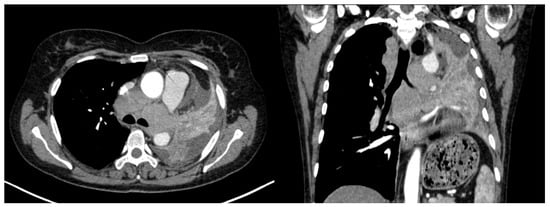

Regarding lymph node involvement, there was an equal distribution in the ADC group (50%), while in the SQCC group there was a significantly higher proportion, with 19 cases (87%) presenting with lymph node involvement (Figure 11) with p = 0.02. In the current study, staging was conducted using the criteria of the Eighth Edition Lung Cancer Stage Classification [30]. Some examples of lymph node involvement can be found in Figure 12 and Figure 13.

Figure 13.

Axial and coronal CT of a left central SQCC with multiple mediastinal lymph nodes involving all mediastinal lymph stations.